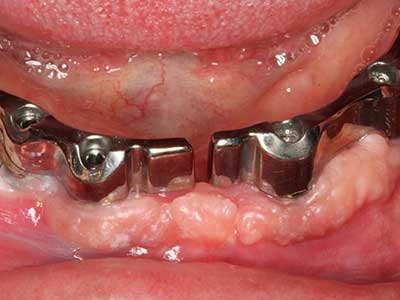

Пиезохирургията има допълнителни предимства при събиране на костни блокове. В допълнение към високата прецизност при остеотомията, описана по-горе, употребата на фините режещи накрайници значително намаляват загубата на материал. Голяма загуба на материал по време на събиране може да се очаква с дебелите накрайници, особено при употреба на борери Линдеман (Lakshmiganthan, Gokulanathan et al. 2012). Базалното разделяне, което е необходимо, особено за присадка на блок при ретромолар, е улеснено от специално създадени правоъгълни триони. В резултат на това, пиезохирургията е разглеждана като прецизна, улеснена и безопасна процедура за събиране на костни блокове в ретромоларното пространство (Happe 2007) (Фиг. 1-12).

Когато се извършват хирургични процедури върху кост в непосредствена близост до чувствителни структури като кръвоносни съдове или нерви, ротиращите инструменти създават значителен риск за ятрогенно нараняване. Пиезоелектрическите апарати могат да бъдат от помощ при препарация на костно покритие и отстраняване на твърда кост близо до нерви, особено за оголване на нервите след ятрогенно нараняване, както и по време на латерализация на нервите за резекционни и реконструктивни процедури или поставяне на имплант (Фиг. 17-20). Лекият контакт между пиезонакрайника и нерва по принцип не води до нараняване, но ако действате непредпазливо с трионообразни движения или приставки за остатъчен костен субстрат, може да причините временно или перманентно увреждане на нерва. Въпреки това, рискът от увреждане се счита за много по-малък, отколкото при употреба на триони или ротиращи инструменти (Pereira, Gealh et al. 2014).